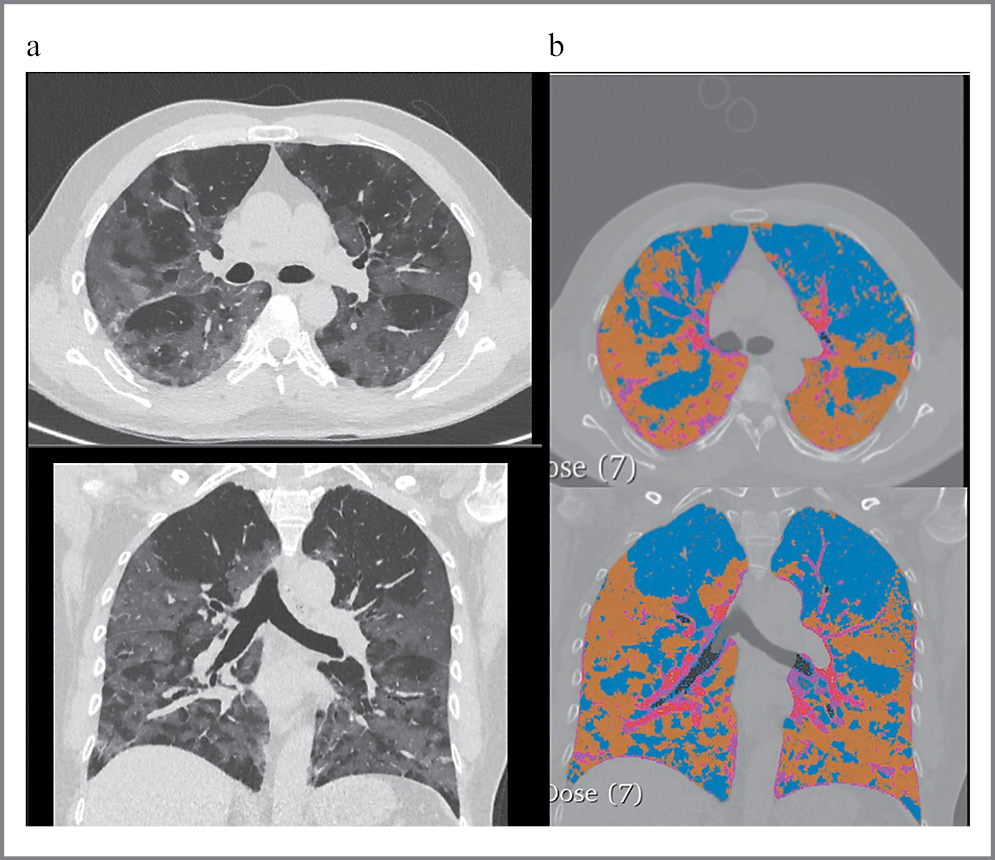

По данным КТ ОГК у всех пациентов в острой фазе заболевания выявлены изменения, типичные для COVID-19. У всех пациентов отмечался двусторонний процесс. Патологически измененная ткань занимала 67,2% общего объема легочной ткани.

Основная доля (45,4%) патологических изменений в период острой фазы заболевания приходилась на «матовое стекло» и несколько меньше (21,3%) – на зоны консолидации (рис. 5).

Рис. 5: а – КТ ОГК (аксиальная и фронтальная реконструкции) в острой фазе заболевания; b – КТ легких, обработанная с помощью программного обеспечения Lung CT analysis for COVID-19.

Примечательно, что при повторных обследованиях, как в ранний период после выписки из стационара, так и в отсроченный, патологические зоны значительно регрессировали и изменилась сама структура патологических паттернов.

У пациентов, проходивших динамическое КТ-обследование в ранние сроки после перенесенной коронавирусной инфекции (с 30 по 60-й день), на долю патологически измененных зон приходилось уже 30,9%. Из них «матовое стекло» занимало 17,8%, консолидация – 3,5%, а появившиеся ретикулярные изменения – 9,45% (рис. 6).

Рис. 6: a – тот же пациент (см. рис. 5). КТ ОГК (аксиальная и фронтальная реконструкции) в динамике через 30 дней; b – КТ легких, обработанная с помощью программного обеспечения Lung CT analysis for COVID-19.